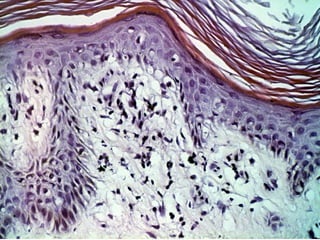

Аутосенситизационный дерматит при венозной

недостаточности голеней

При несостоятельности вен нижних конечностей местно

могут развиваться нарушения, похожие на экзему –

стазис дематит («венозная экзема». У некоторых больных

на любых других участках кожи развивается

аутоиммунный дерматит, который называют

аутосенситизационным.